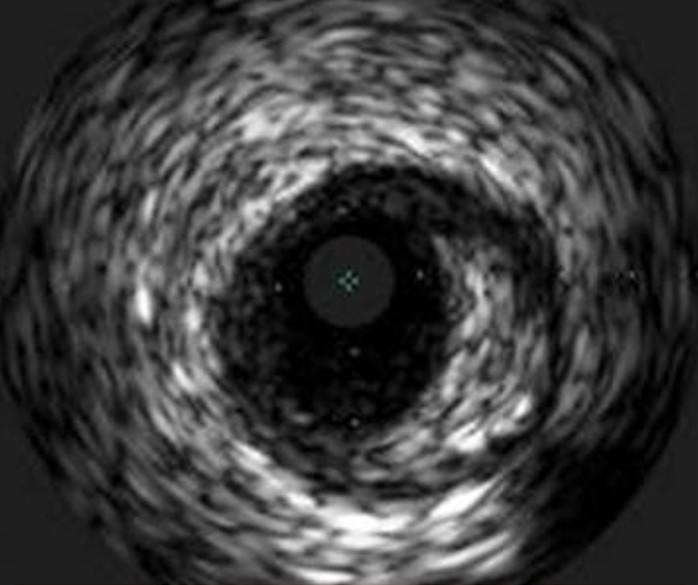

Catéter para toma de imágenes coronarias Opticross de 40 MHz vs. Catéter para toma de imágenes coronarias Opticross de 60 MHz

El Catéter para toma de imágenes coronarias Opticross de 60 MHz proporciona una mayor visibilidad del stent con una resolución más clara para confirmar la aposición adecuada del stent a la pared del vaso.

OPTICROSS 60 MHz

Catéter de imágenes OPTICROSS HD 60MHz

Resolución axial: 22 µm